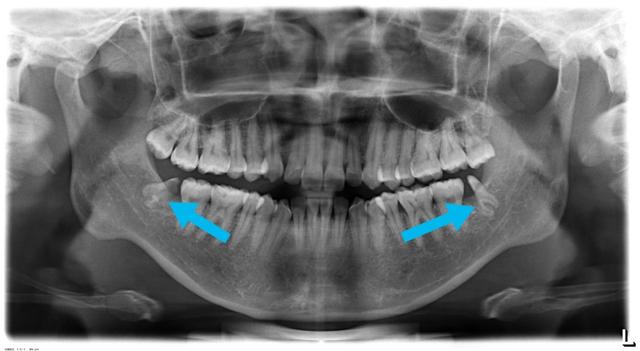

2、牙根离神经管很近的智齿,建议用两个步骤来处理,否则不拔

(截冠半年后牙根已经离开神经管,这时候拔掉牙根很安全)